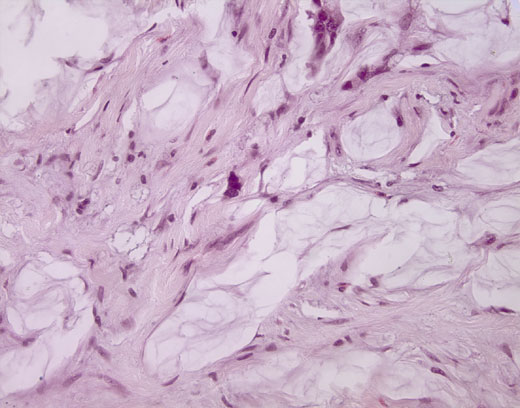

Cross-section #21 - 40X